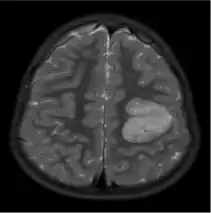

The neurological features of AG tumors are visible via CT scanning or MRI. A clear indication of AG may appear as well-delineated, solid, T2-hyperintense, non-enhancing cortical lesions located in the temporal or frontal lobes in MRI.[1] Another diagnostic trait is a stalk-like extension to adjacent brain ventricles.[13] These traits are similar to low-grade gliomas from a radiological perspective.

The results from CT scanning and MRI are different in terms of clarity and effectiveness of diagnosis. AG displays an expansive non-enhancing cortical tumor in CT scanning, whereas MRI shows a relatively clearer appearance of AG and the tumors appear to be infiltrative, well-defined, and hypointense with T1 lesion.[4] T2/FLAIR lesions indicate AG as a tumor tissue with some extension toward the ventricles along vessels.[4] The possibility of cystic-appearing areas exists as well. In some cases, MRI results show an increase in ribbon-like signal on T1W1 lesions.[4] The clear radiographic outcomes of MRI makes it the more widely used option in the diagnosis of AG.[4]